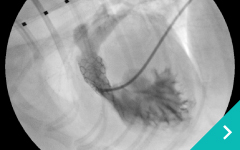

IVRとは、レントゲン透視(X線)や超音波などの画像を使いながら、カテーテルという細い管を体内に通して、病気のある部位を治療する方法です。開胸や開腹をせずに治療できることから、体への負担が少なく、多くのわんちゃん・ねこちゃんにとって優しい選択肢となります。

門脈体循環シャント:異常な血管にコイルやプラグを入れて、血流を正常化します。

コイル塞栓術

血管プラグ